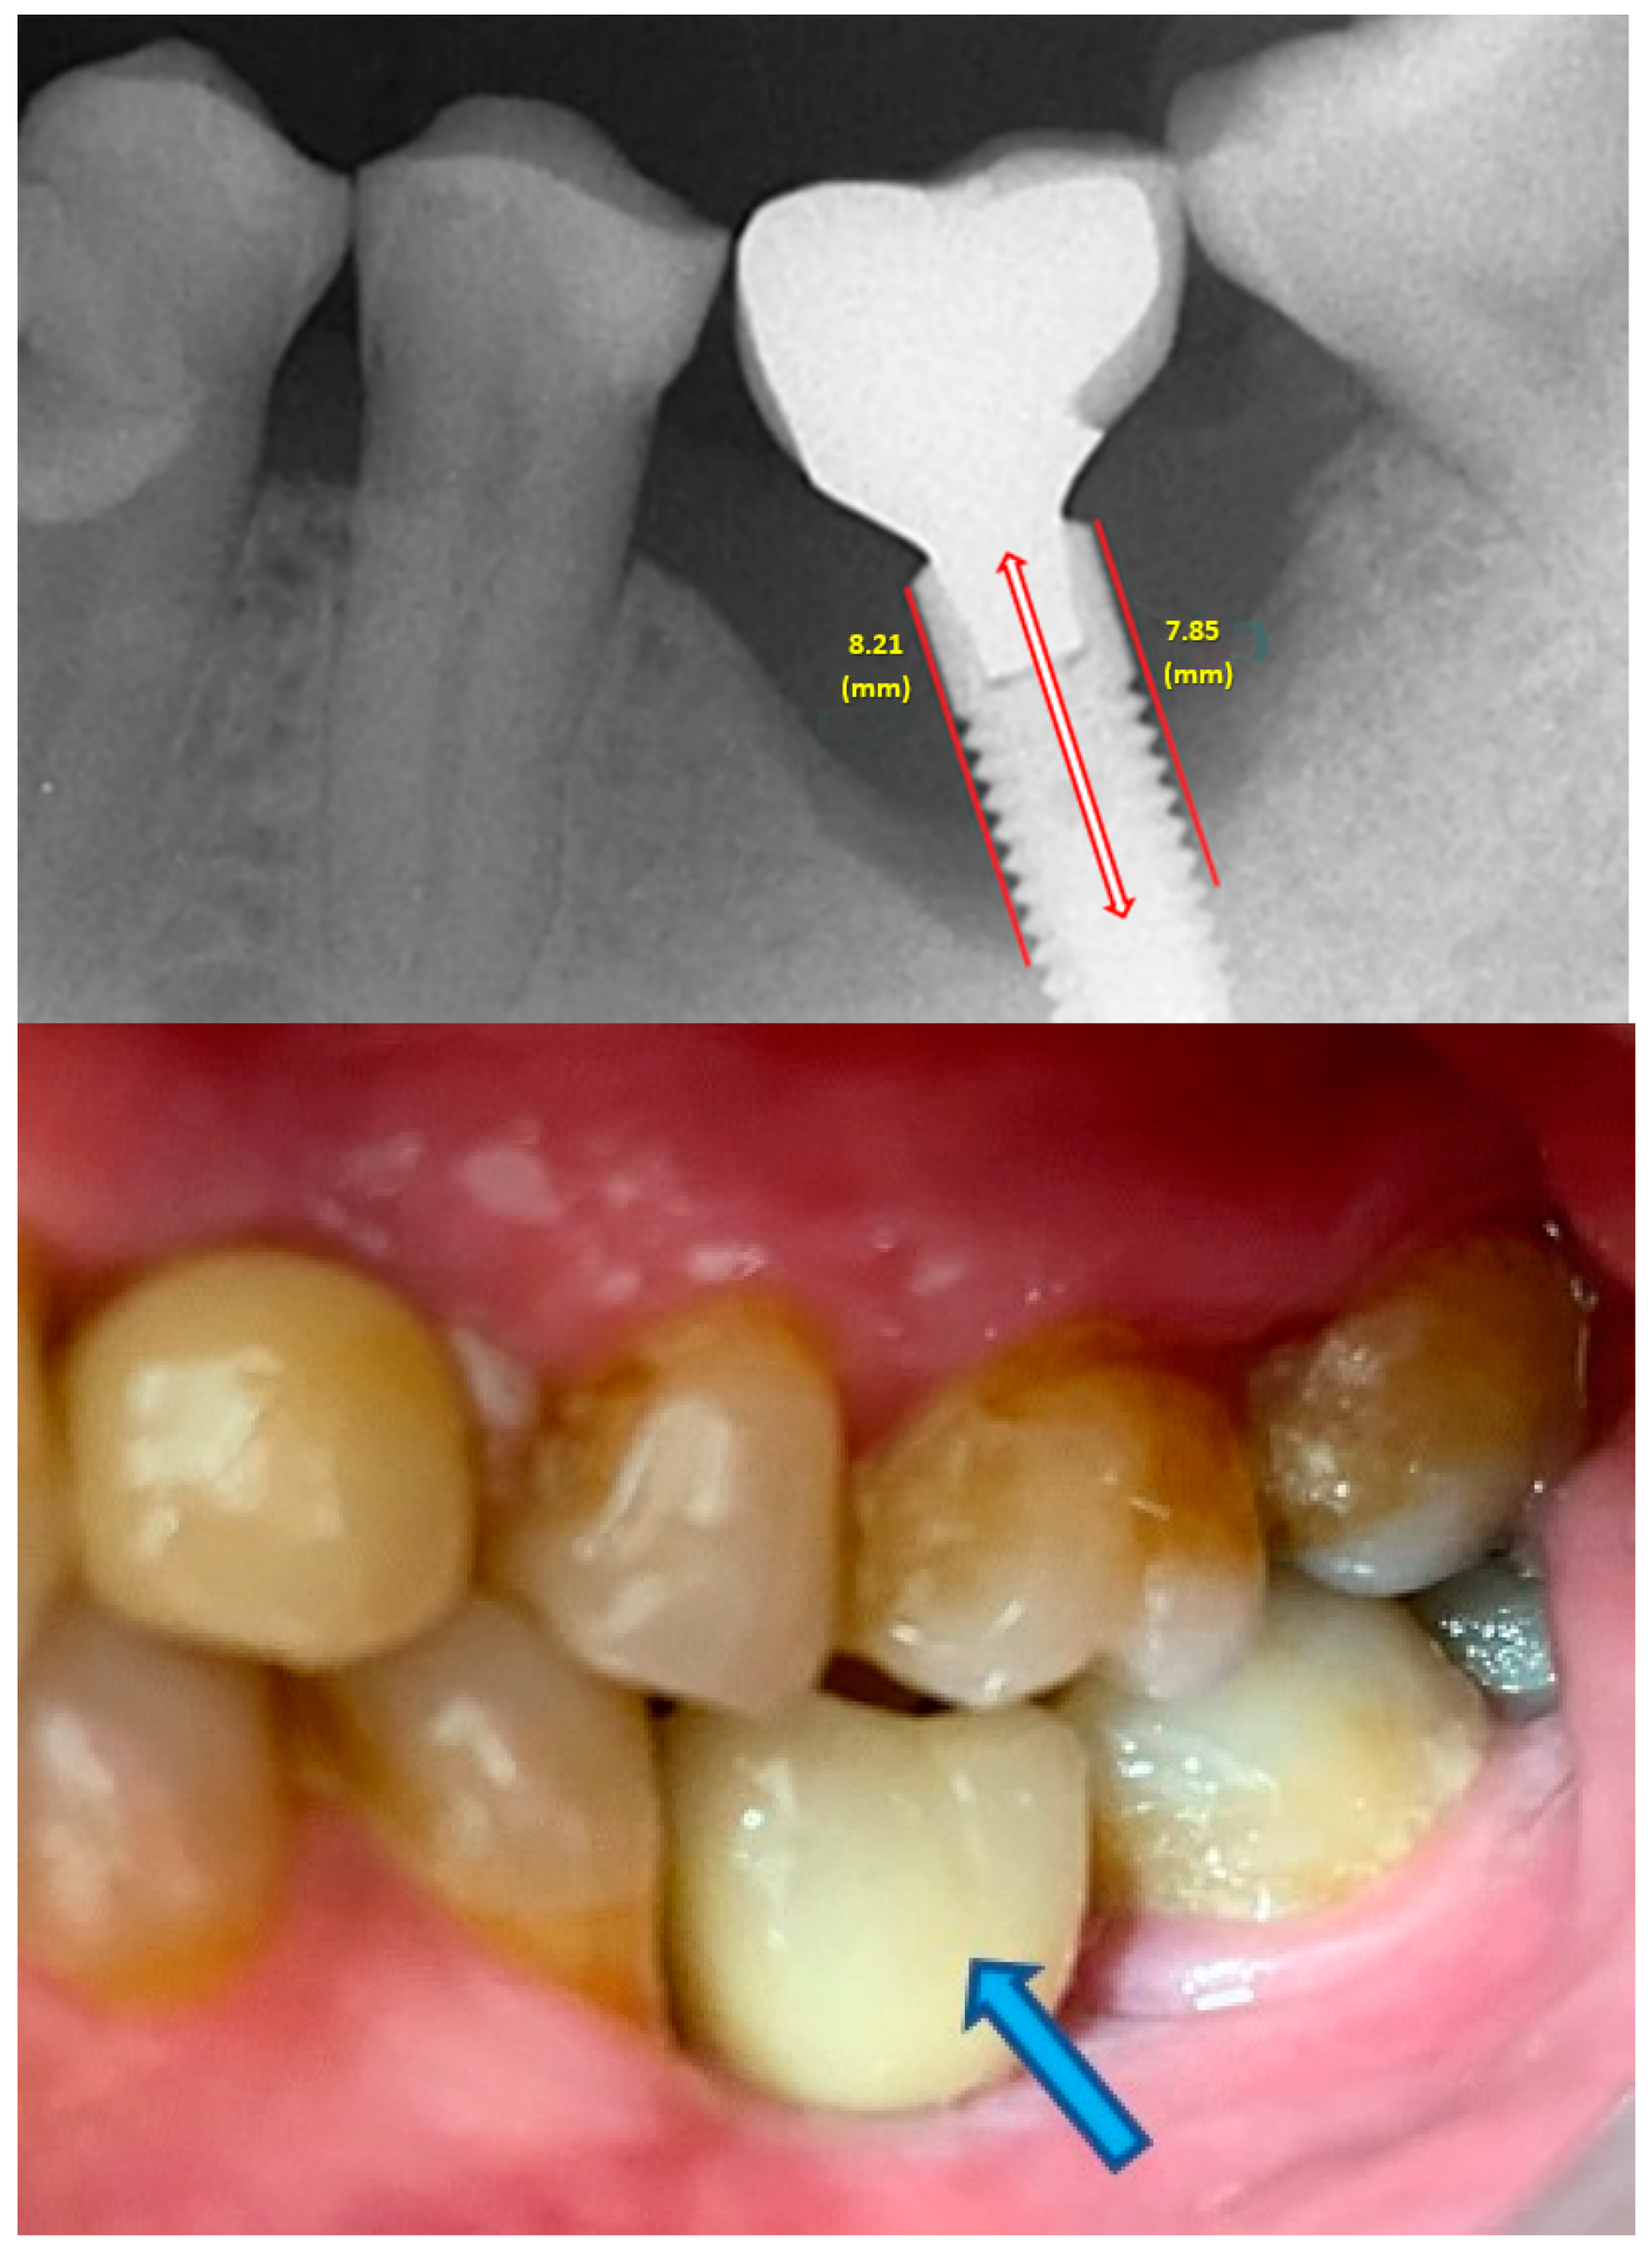

- Measurement of mesial and distal bone loss: Clinically, an increase in the probing depth of the peri-implant pockets, both mesial and distal, was recorded using a calibrated probe with a force of 0.25 N. Radiographically, mesial and distal peri-implant bone height loss was measured using properly performed radiological projections. In fewer than five patients, statistically significant findings in cases of bone loss were difficult to achieve.

- Measurement of the mesial and distal cantilever: The mesial cantilever was significantly greater for the bilateral bone loss group (1833.5 ± 1531.4 µm) compared to the group without MBL (1029.5 ± 968.6 µm) (F = 2.77; p < 0.05). Concerning the effect of the mesial versus distal cantilever, although the mesial cantilever appears to be more favorable, the only article found in the literature regarding this finding is a study by Romeo et al. (2003), which showed that this effect is not always consistent, although the difference is minimal [31].

| Implant length (mm) | 10.0 | 1.2 | 10.7 | 1.4 | 10.6 | 1.7 | F = 1.33; p = 0.268 |